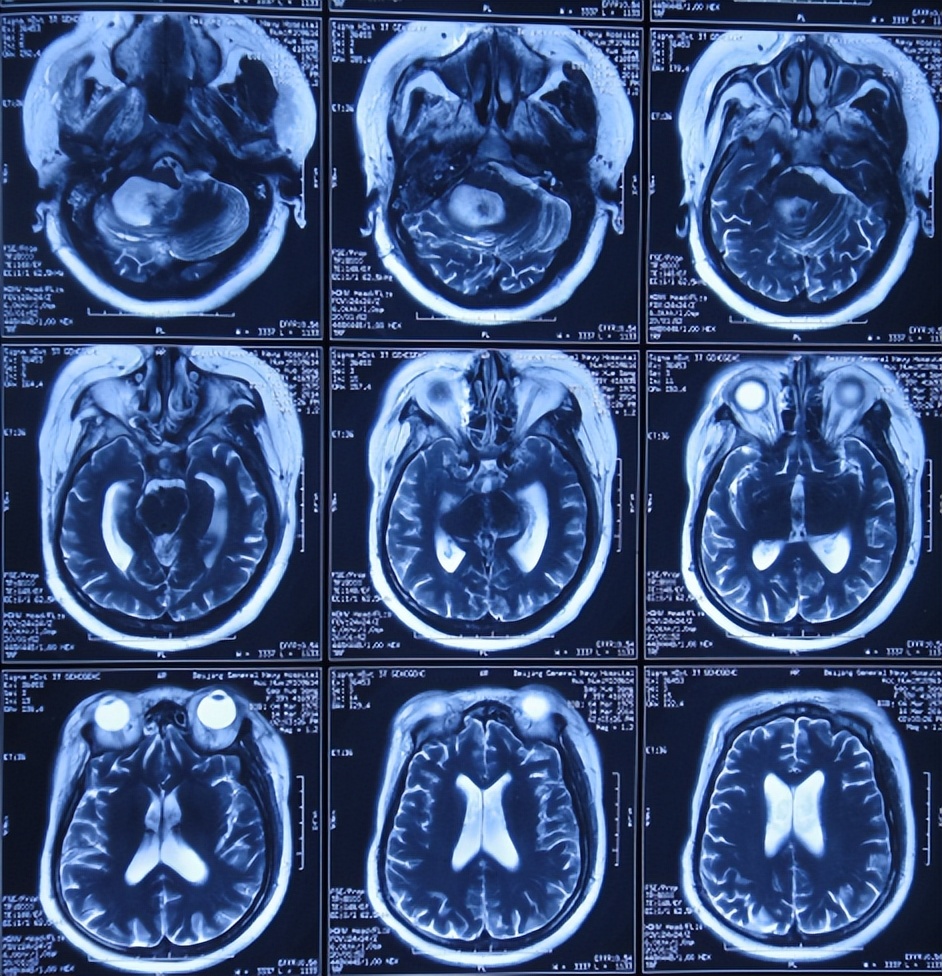

入院时头颅CT示右侧小脑半球低密度影,第四脑室扩张(图-14)。肺片肺部感染(片子丢失);重度贫血,血小板降低,白细胞减少。

图-14:2014年3月20日头颅CT

引流术后8天即2014年4月2日,查头颅CT示四脑室仍有扩张(图-17)。

图-17: 2014年4月2日头颅CT

引流术后20天即2014年4月14日,头颅CT与2014年4月2日比较:右侧小脑半球见片状低密度影;四脑室扩张变小(图-18)。

图-18: 2014年4月14日头颅CT

引流术后41天即2014年5月5日,患者不思进食伴恶心,查头颅CT示四脑室再次扩张变大(图-20)。先观察,如果无改善将行四脑室外引流术。

图-20:2014年5月5日头颅CT

因持续恶心及腹胀不适,2014年5月8日,进行了开颅四脑室腹壁外引流术(图-21)。

图-21:2014年5月8日头颅CT

第四脑室外引流术后15天即2014年5月23日,查头颅CT示四脑室缩小(图-23)。

图-23:2014年5月23日头颅CT

第四脑室外引流术后19天即2014年6月27日,体温正常,但精神差,言语缓慢含糊,查头颅CT示四脑室侧脑室引流管无变化,右侧小脑半球可见片状低密度影;左小脑半球低密度影消失(图-24)。

图-24:2014年6月27日头颅CT

出院后6年即2020年8月31日,当地医院复查头颅CT示无异常(图-31)。

图-31:2020年8月31日头颅CT